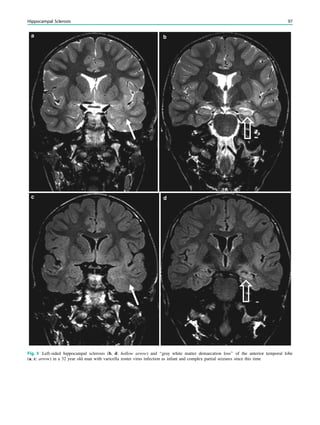

Contents

1 Introduction.......................................................................... 29

2 Theoretical Considerations................................................. 29

3 Clinical Practice................................................................... 30

4 Requirements for MR Quality........................................... 32

4.1 Orientation ............................................................................. 32